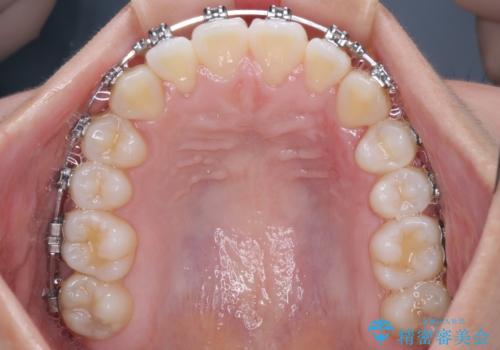

前歯のデコボコを楽して改善 ワイヤー装置による矯正治療

- メタルブラケット

- 1年2ヶ月

- 前歯のデコボコを治したいとのことで来院された患者様です。

インビザラインによるマウスピース矯正も適用となる歯列でしたが、できる限り楽して、短期間で治したいとのことで、ワイヤー装置にて矯正治療を行うこととしました。